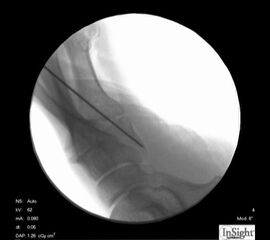

Operationstechnik (Fotos)

Zum Lesen der Bildbeschreibung und zur Vollansicht bitte die Bilder anklicken.

Abbildung 2

Abbildung 3

Abbildung 4

Abbildung 5